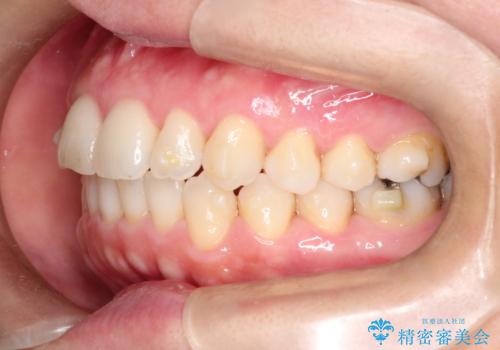

【インビザライン 】前歯のガタガタを治したい

- 前歯のガタガタを主訴に来院されました。

インビザライン で治療しました。途中は使用時間が20時間を切ることもありましたが、それでも頑張って使っていただき1年半で矯正終了することができました。